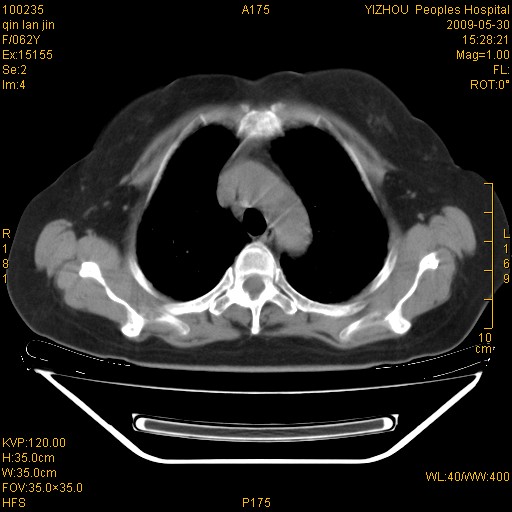

标题: CT20268:肺泡癌?间质性肺炎? [打印本页]

标题: CT20268:肺泡癌?间质性肺炎?

女,62岁,近二年经常咳嗽,近二个月,消瘦、乏力。

纵隔淋巴结大,须排外癌性淋巴管炎